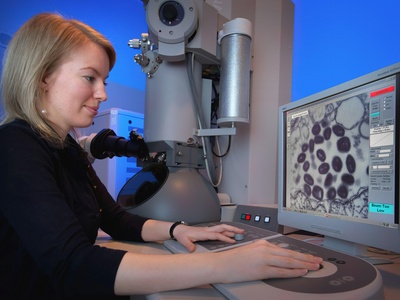

Images and Descriptions